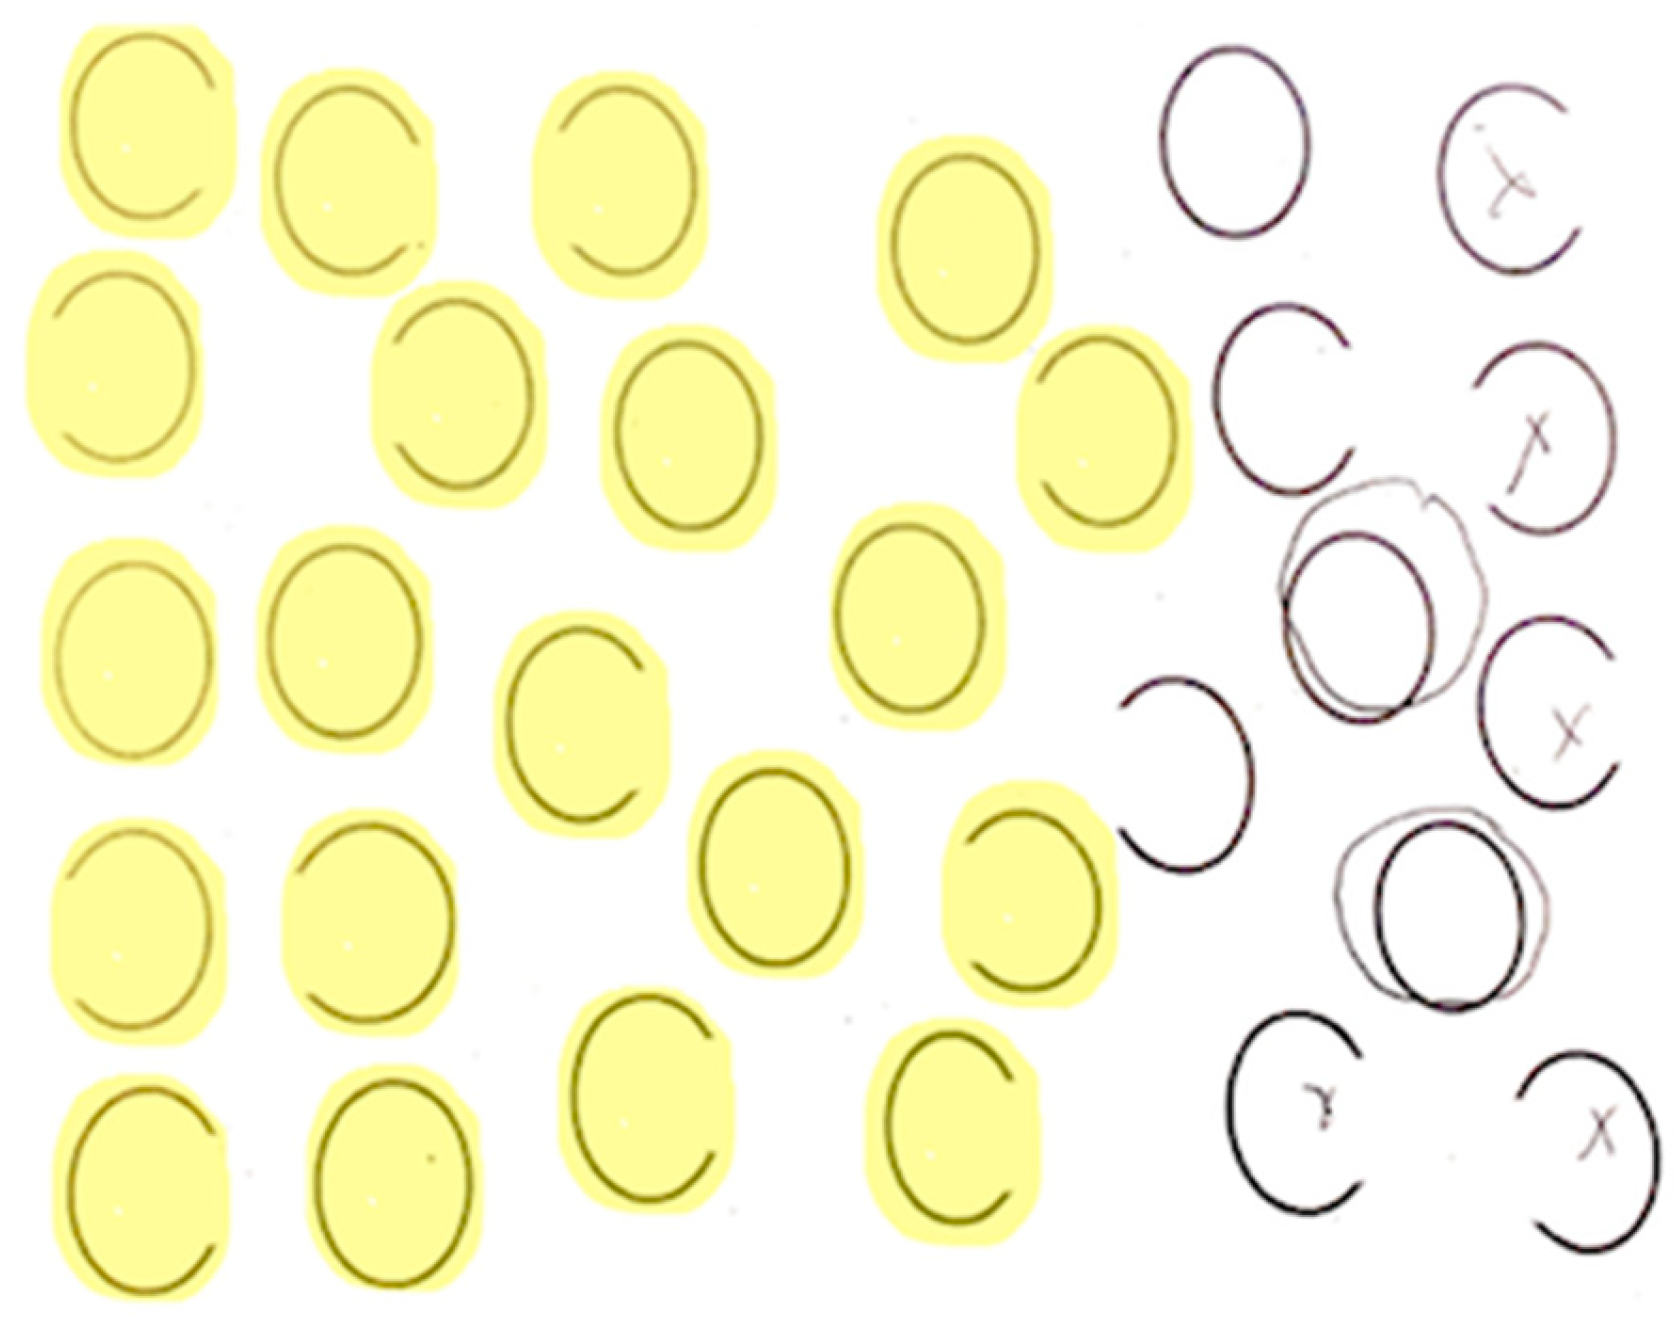

Each participant completed a neglect task with 30 ovals: 10 full, 10 with a gap on the left, and 10 with a gap on the right (adapted from Ota). Participants were asked to circle full ovals and cross out ovals with a gap on either side. We defined VCN as >10% of the total number of ovals left unmarked after the most extreme mark on the contralesional side (Figure 2) and SCN as incorrectly marking >10% of contralesional gaps (Figure 3). All participants completed neglect testing and brain MRI within 5 days of stroke onset.

Figure 3. Example of right stimulus-centered neglect (SCN). Participants were asked to circle full ovals and cross out (put an X on) ovals with a gap on either side. The yellow highlighted items indicate errors. Errors were gaps (on the right) that the patient failed to notice.